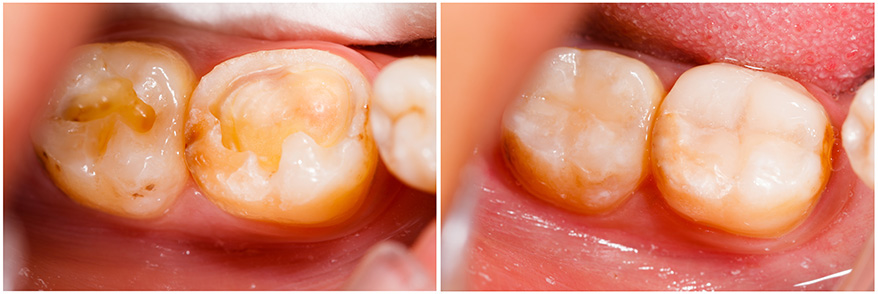

Dental resins Mexico, is the appropriate technique when what you are looking for is something conservative and aesthetically pleasing for any of your teeth that have cavities or small imperfections, dental resins are the perfect choice.

Teeth damaged by cavities require to be filled, these fillings are very resistant to chewing and blend in with your teeth because they are white.

White fillings are composed of a synthetic resin material that hardens once exposed to halogen light. Technological advances make it possible to reconstruct front teeth as well as place fillings in molars without them being noticed, thus achieving aesthetics and functionality.

Mexico Dental resins can be an excellent and healthy alternative that you and your dentist should evaluate, if you have a cavity, cracks or metal fillings in your teeth. Metal fillings or amalgams can easily be replaced by dental resins, giving you a more aesthetically pleasing smile.